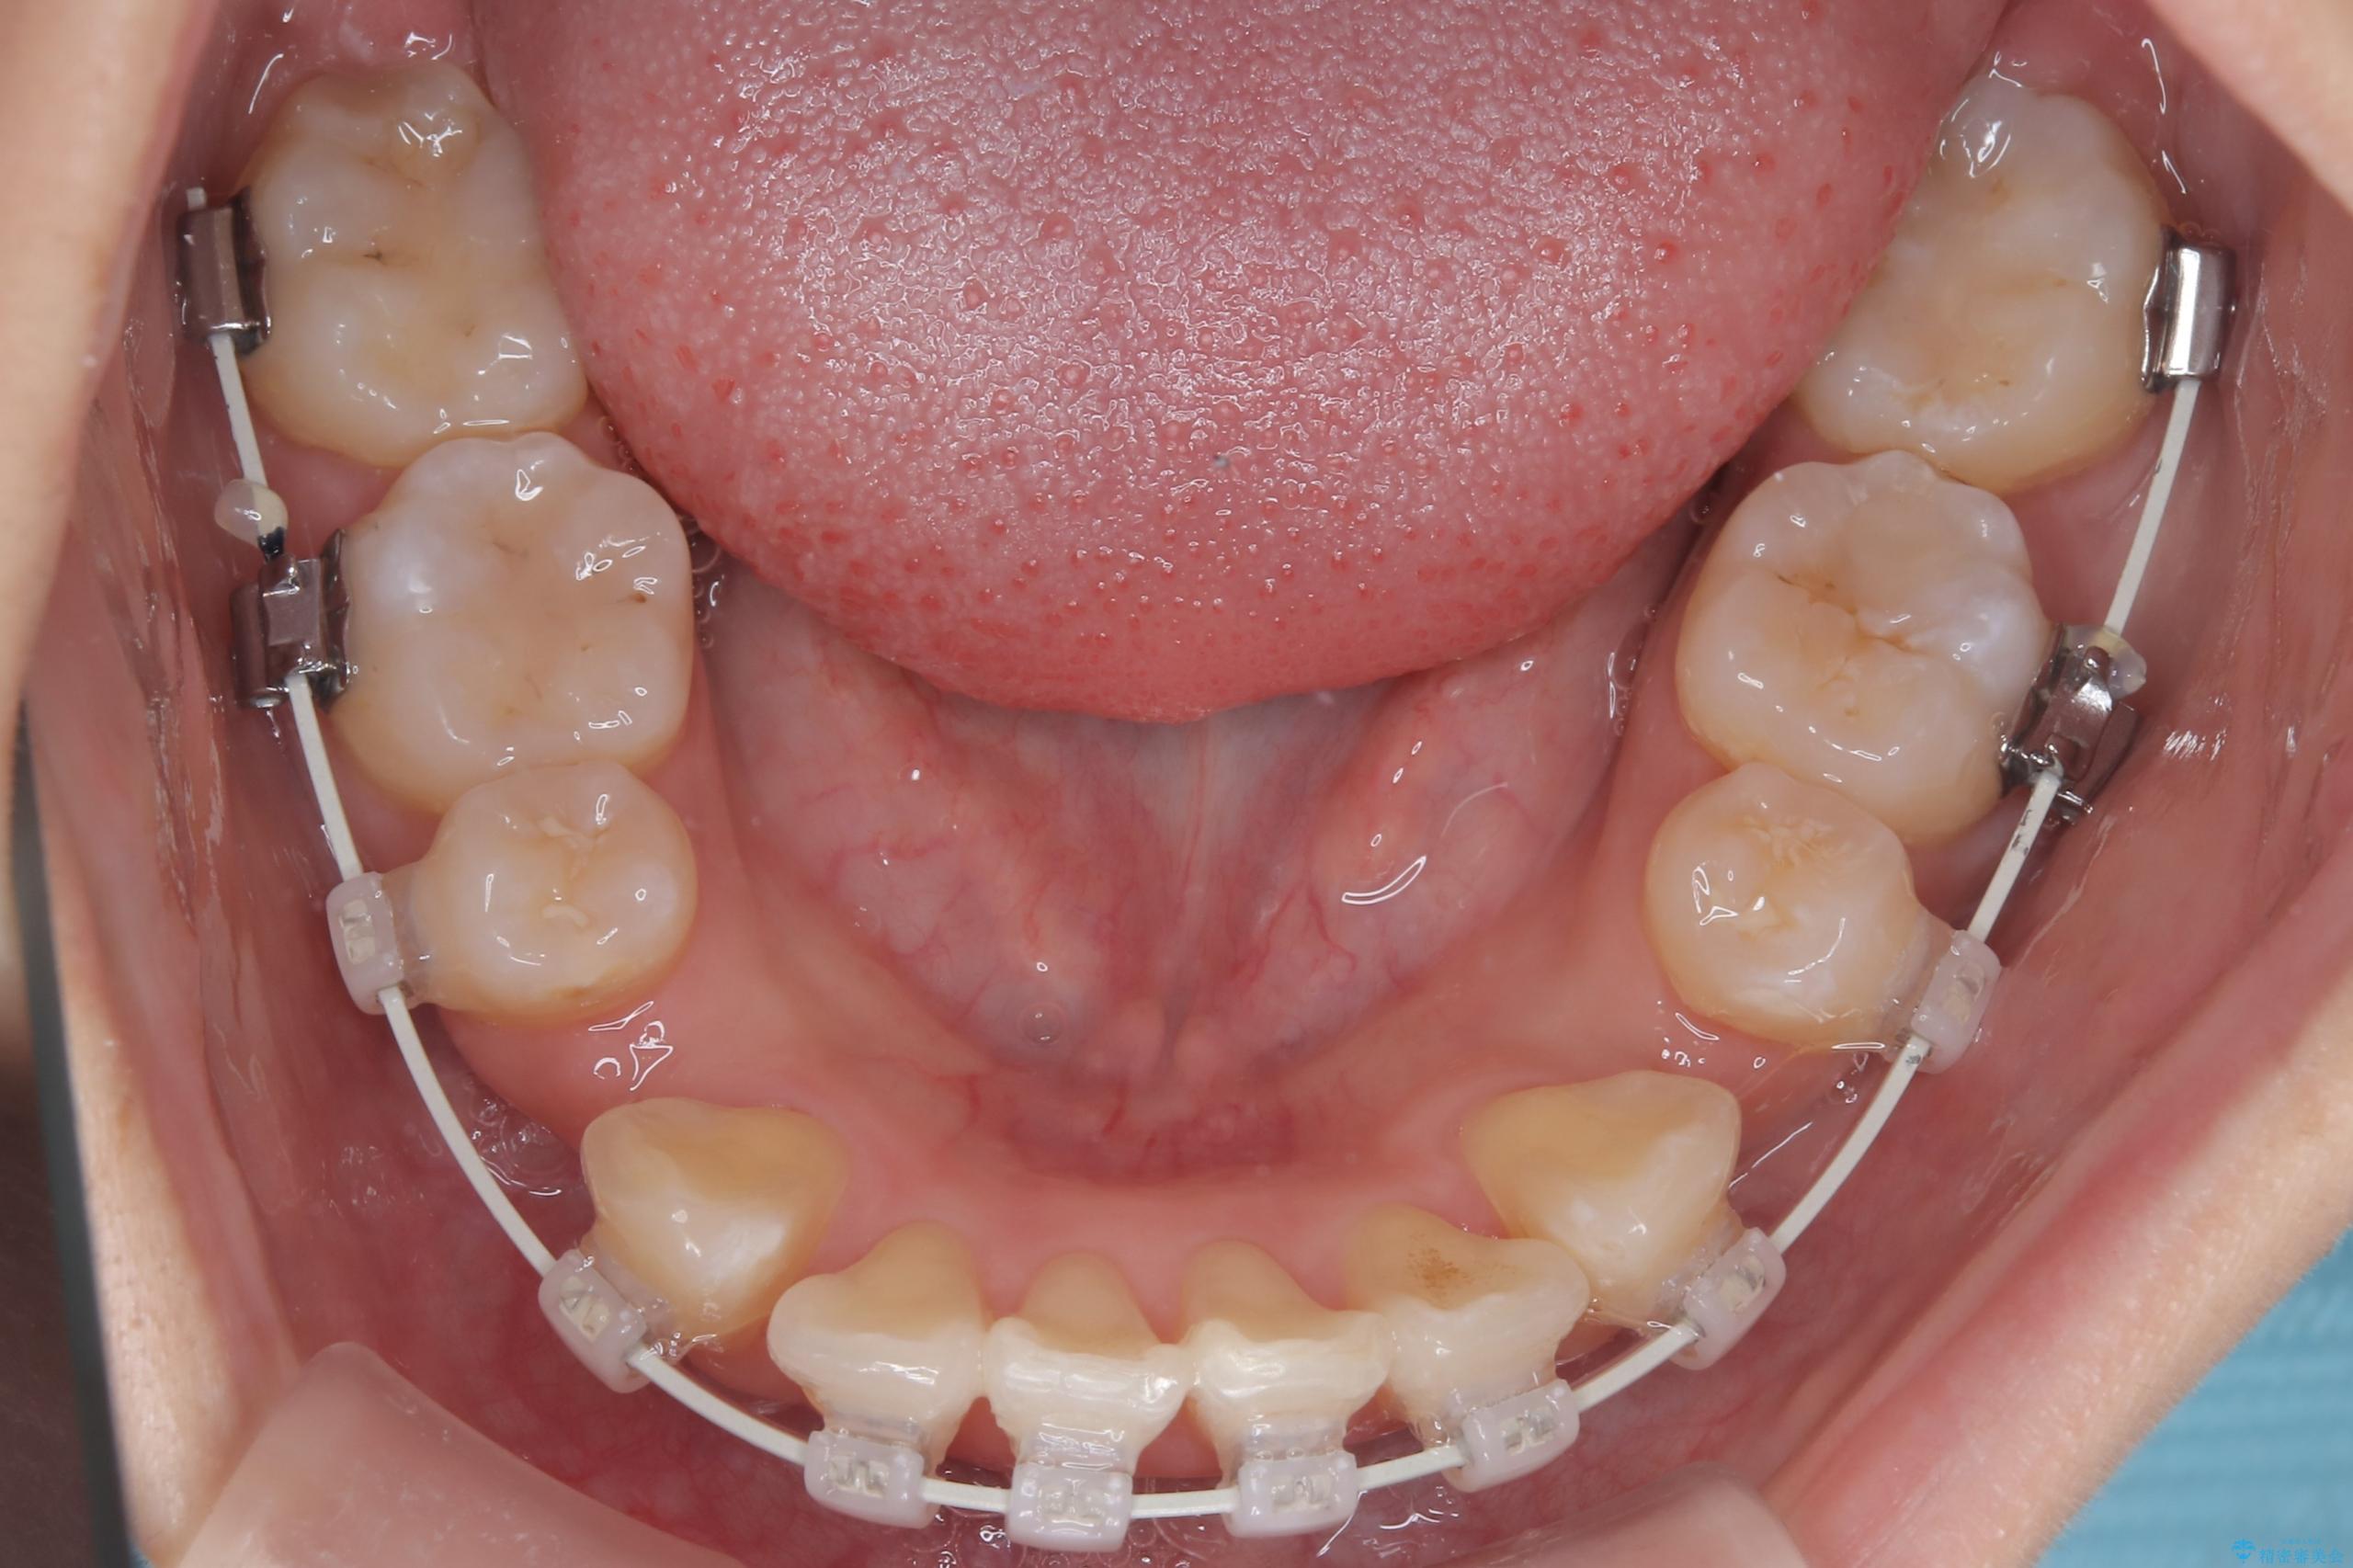

- 八重歯(叢生)と、上下の歯の中心線(正中)がずれていることを主訴にご来院されました。精密な検査の結果、歯列全体のスペースが大幅に不足しており、八重歯を正しい位置に配列し、正中のズレを改善するためには、上下左右の第一小臼歯を抜歯する必要があると診断。装置には、目立ちにくい審美ワイヤーを使用し、見た目を気にせず、機能性と審美性が完璧に整った咬み合わせを目指す治療計画を立案しました。

今回の矯正治療では、まず計画通り上下左右の小臼歯4本を抜歯し、八重歯や正中のズレを解消するための十分なスペースを確保しました。装置には、目立ちにくい白いブラケットとワイヤーを使用した審美ワイヤー矯正を採用。

八重歯: 突出していた八重歯を歯列内に誘導し、デコボコを解消しました。

正中のズレ: 歯を左右対称に移動させることで、上下の歯の中心線を正確に合わせ、顔全体のバランスも改善しました。